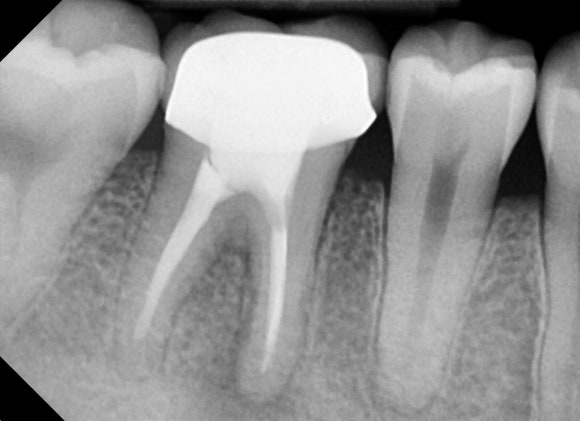

20241224

국가고시를 앞두고 있는 젊은 남성분입니다.

오른쪽 아래 신경치료를 하고 크라운을 씌운 치아가 있습니다.

얼마전부터 잇몸이 붓고 아파서

구강외과에서 고름을 째고 소독을 받았지만

다시 고름이 차기 시작하셨다고 합니다.

- 신경치료 기원의 고름은 째고 소독한다고 해결되지 않습니다. 반드시 재신경치료나 발치 같은 근본적인 치료가 필요합니다.